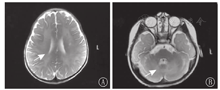

实验室检查:血常规、生化、心肌酶谱、血氨、丙酮酸、甲状腺功能未见异常;脑脊液常规、生化、培养、涂片均阴性;生长激素2.33 μg/L,总睾酮0.69 nmol/L,皮质醇83 nmol/L(正常值138~569 nmol/L);血尿遗传代谢性疾病筛查未见异常。头颅磁共振成像(MRI)检查示双侧大小脑半球白质区弥漫性异常信号,考虑遗传代谢性脑白质病(图2)。视频脑电图示背景活动偏慢,左侧额、颞区慢波发放。眼底检查提示双侧视神经有萎缩倾向。牙片提示牙列不齐及出牙不全。听力诱发电位双侧Ⅰ波潜伏期延长、双侧听性脑干反应(ABR)主观听阈轻度增高;视觉诱发电位示双侧P100潜伏期延长。

注:T2WI:T2加权像 T2WI:T2 weighted image